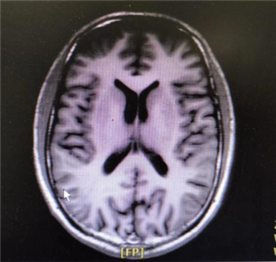

正常的脑室影像 扩大的脑室影像

诊断:主要依靠影像学检查。头部计算机断层扫描(CT)或磁共振成像(MRI)可以清晰显示脑室是否扩大及可能的梗阻部位。对于疑似正常压力脑积水的患者,医生可能会建议进行脑脊液放液试验等进一步评估。